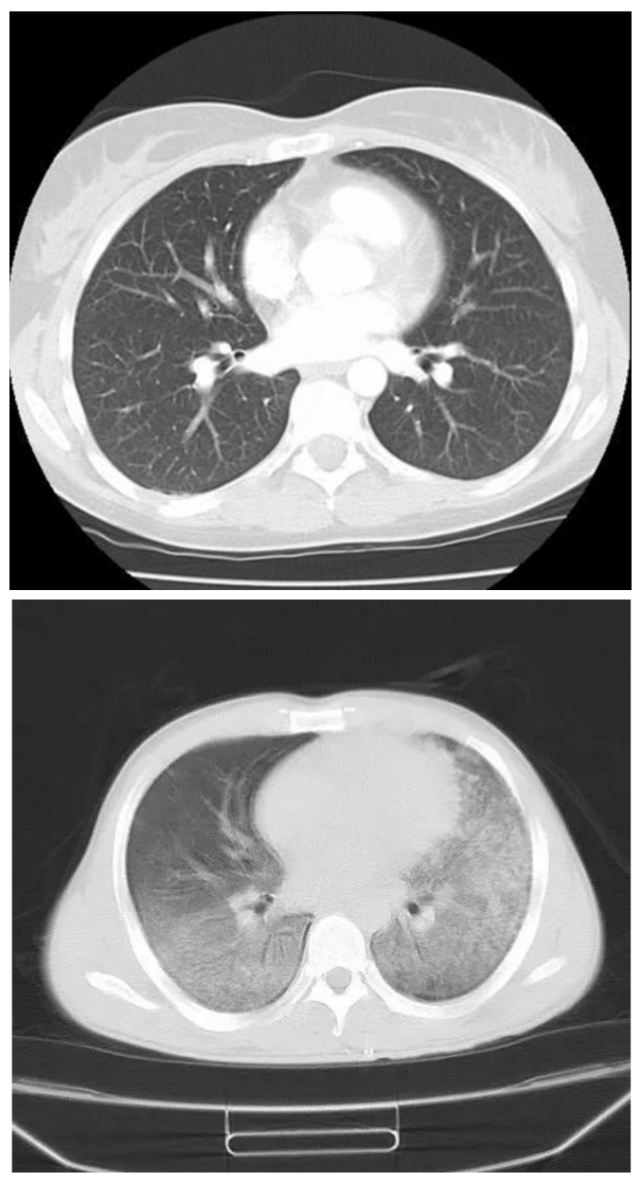

“白肺”与“黑肺”反映肺内密度的高低

正常人肺内都是气体,所以密度低,X射线衰减的就少,最终显示的图像为黑色。

而一旦肺内充满分泌物或者有占位性病变,密度就会增高,X射线衰减的就多,最终的图像显示为白色。

如下图的胸部CT结果示:上面的为正常的胸部CT,为“黑肺”,下面的为肺炎的CT表现,即为“白肺”。